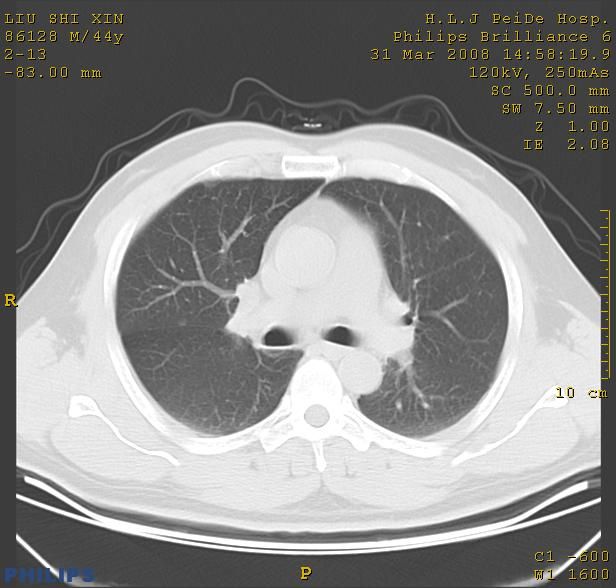

标题: CT13096:请分析胸膜下结节的影像基础是什么 有病理结果 [打印本页]

标题: CT13096:请分析胸膜下结节的影像基础是什么 有病理结果

瘢痕挛缩,胸膜牵拉,血管纠集扭曲,上叶前段支气管显示欠清,周围散在斑片影,以纵隔旁肺癌可能性大。请穿刺检查。

中心型肺癌并阻塞性肺炎及肺内转移

中心型肺癌并阻塞性肺炎、两肺及胸膜多发转移。

结节灶与血管末梢相通象转移灶;小三角状尖部有纤维索是胸膜拉扯征;纵隔旁大片实性影有点状钙化;周围有名显纤维瘢痕征可考虑瘢痕癌

本病例有病理结果是,鳞状上皮癌,胸膜下结节影病现诊断的肿大淋巴结,谢谢大家分析,请问胸膜下结节是肿大淋巴结怎么解释